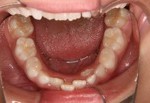

通常小学校に入る前に下の乳前歯が抜けて永久歯が生えてきますが、その時点で歯がデコボコになっているのに気が付くことが多いようですが、このような場合は受け口や交叉咬合といった症状がなければすぐに治療を始める必要はありません。